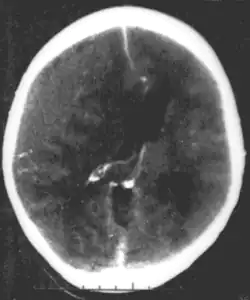

Brain trauma in the developing human is a common cause (over 400,000 injuries per year in the US alone, without clear information as to how many produce developmental sequellae)[41] of neurodevelopmental syndromes. It may be subdivided into two major categories, congenital injury (including injury resulting from otherwise uncomplicated premature birth)[6] and injury occurring in infancy or childhood. Common causes of congenital injury are asphyxia (obstruction of the trachea), hypoxia (lack of oxygen to the brain), and the mechanical trauma of the birth process itself.[42]